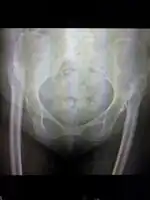

Anterior-posterior (AP) X-rays of the pelvis, AP and lateral views of the femur (knee included) are ordered for diagnosis.[13] The size of the head of the femur is then compared across both sides of the pelvis. The affected femoral head will appear larger if the dislocation is anterior, and smaller if posterior.[14] A CT scan may also be ordered to clarify the fracture pattern.

Reimer's migration index can be used to indicate hip dislocation. The migration index (MI) is normally less than 33%.[18]